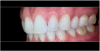

Fig 4. Left: This intraoral photograph taken with only a smartphone shows image distortion and poor color rendering. Right: This intraoral photograph was taken with a DSLR camera with an external flash and is much higher quality.

Figure 4